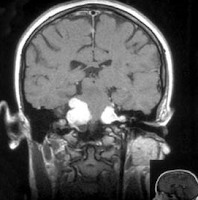

Ironicamente, apesar da maioria das premissas básicas da frenologia terem sido consideradas pseudociência, as leituras dos comportamentos e a sua relação com o crânio não foram. O princípio de que as funções específicas cerebrais estão localizadas em topografias determinadas é agora conhecimento comum demonstradas por técnicas modernas de imagem, como a ressonância magnética funcional (FMRI). Esta doutrina que possibilita a visualização precisa de uma determinada função quando ela está sendo realizada é chamada de localizacionismo cerebral.